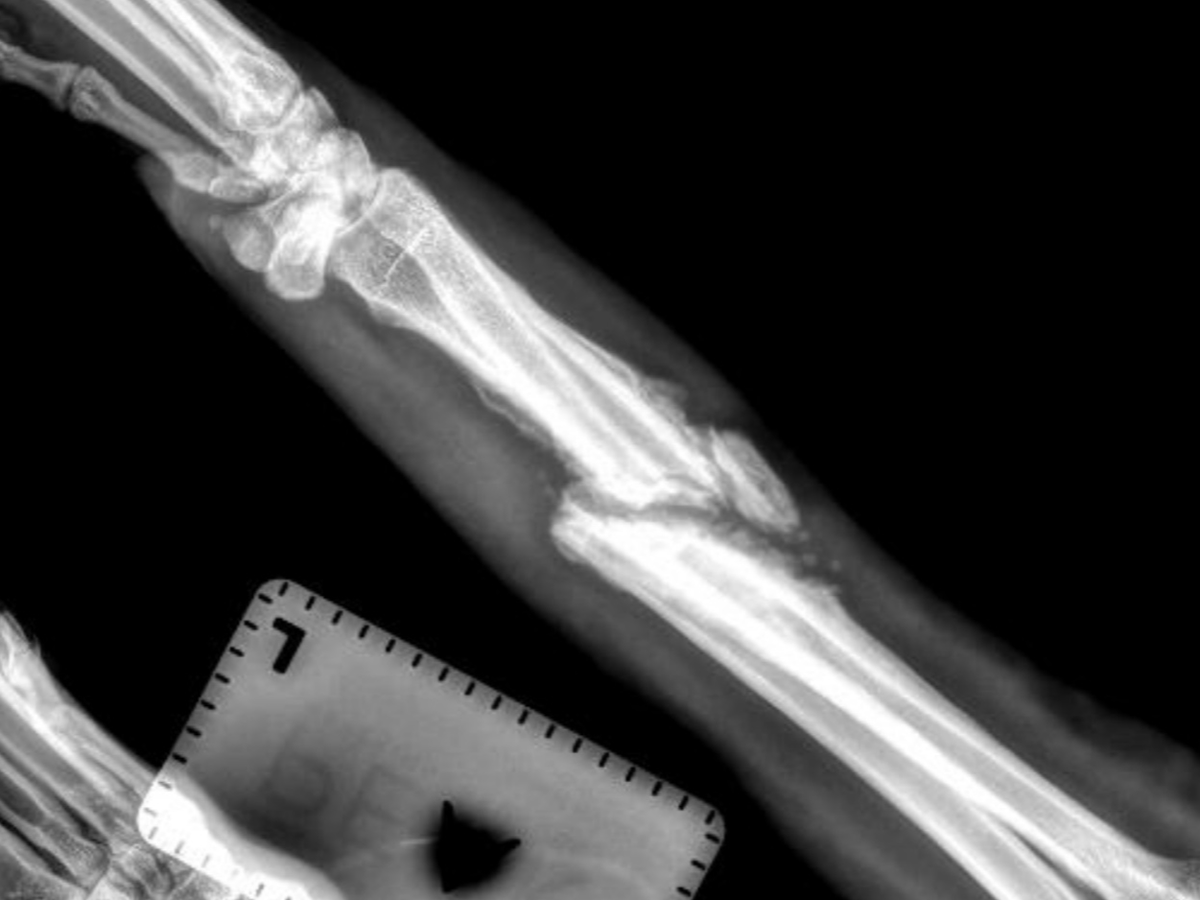

I found Keno (formerly Louise) days after losing my last rescue, Maci, to terminal lung cancer. It was quick, and I wasn't looking for another dog, but then I saw an urgent post asking if anyone could help. Keno was on the "Kill list," and was days away from being euthanized. On top of that, he had a broken leg; the extent of the break was unknown at the time as the shelter that had him would not disclose the severity. After seeing the X-rays, it is tragic he sat there for 2 months in this condition.

Unfortunately, at this point, our vet is recommending amputation due to the severity of the break and because it went without proper treatment for so long. Surgery is still not out of the question but will be equally as expensive.